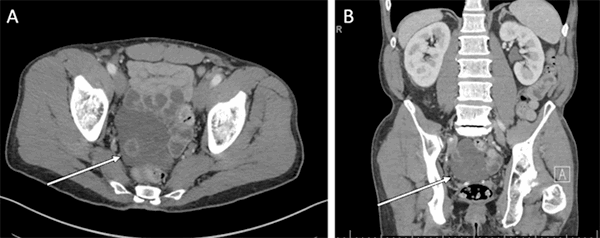

A 54-year-old man with a history of hepatitis C, type I diabetes mellitus, hypertension, alcohol abuse, tobacco abuse, and chronic obstructive pulmonary disease was referred for incidental findings on imaging concerning for PMP secondary to low-grade appendiceal mucinous neoplasm (LAMN). He presented with several years of intermittent symptoms of decreased appetite, unintentional weight loss, lower abdominal pain, constipation, nausea, and vomiting. He denied ever to have blood in his stool. He had a recent colonoscopy that showed a total of five successfully snared sessile, serrated polyps negative for dysplasia measuring between 3 mm and 10 mm located between the sigmoid and ascending colon. He had a normal physical examination. Laboratory results showed a hemoglobin of 12.3 g/dL, CA-125 of 11 U/mL (normal <34 U/mL), CEA of 5.2 ng/mL (normal 0.0-5.4 ng/mL), CA 19-9 of 13 U/mL (normal <34 U/mL). CT scan displayed an 8 cm x 7 cm x 5.7 cm multilobulated, low-density non-enhancing mass encasing loops of small bowel without obstruction (Figure 1A). No metastatic disease or other peritoneal implants were appreciated, but there was a concern for intraabdominal mucus in the left upper quadrant. The base of the appendix was partially visualized and showing a normal appearance, but the tip was not able to be identified (Figure 1B). Differential diagnoses based on imaging included lymphangioma and low-grade pseudomyxoma peritonei. After a multi-disciplinary tumor board discussion, the decision was made to proceed to the operating room for resection due to the potential of PMP as malignancy could not be excluded, and the patient was symptomatic from the lesion.

Figure 1. Preoperative computed tomography (CT) imaging. A) Axial imaging showing presence of multi-loculated, cystic abdominal lesion(white arrow pointing to pelvic mass). B) Coronal view of same abdominal CT scan (red arrow pointing to partially visualized appendix)